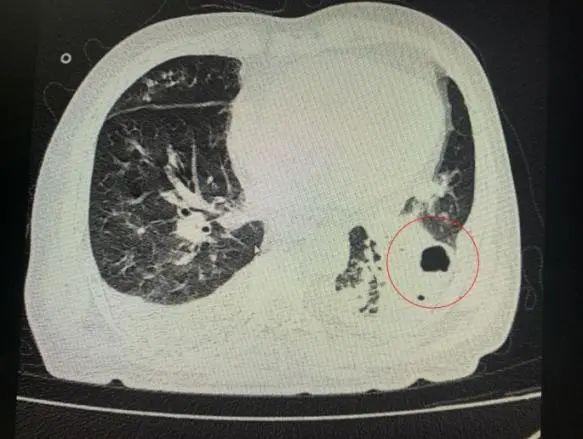

番禺院區(qū)呼吸內(nèi)科何夢(mèng)璋主任接診后,對(duì)鐘叔進(jìn)行詳細(xì)檢查。此時(shí),鐘叔的病情已經(jīng)十分危急,由于不能自主呼吸,他帶上了呼吸機(jī)輔助呼吸調(diào)節(jié)??吹界娛逍仄瑫r(shí),醫(yī)護(hù)人員頭皮也一陣發(fā)麻,胸部CT可見雙肺多發(fā)的炎癥浸潤(rùn)、雙肺多發(fā)空洞。通俗來說,鐘叔的肺部已經(jīng)被病原體蠶食,啃出個(gè)大小各異的洞!可怕的是,這種病變對(duì)肺功能的破壞是性、不可恢復(fù)的。根據(jù)鐘叔病史以及胸部CT結(jié)果,終診斷為“吸入性肺膿腫”。

鐘叔的肺部被病原體蠶食,啃出個(gè)大小各異的洞。